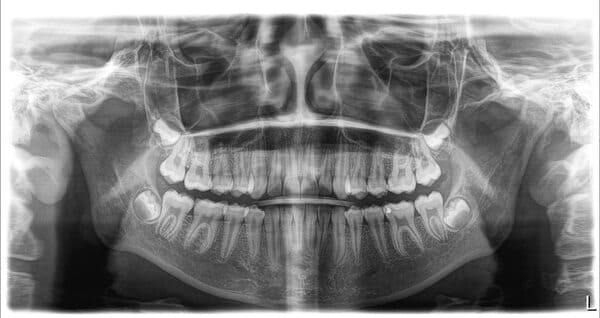

Ми рекомендуємо видаляти зуби мудрості, поки їхні корені ще не сформовані. Зазвичай це відбувається в підлітковому віці. Таке втручання є менш травматичним і значно простішим, ніж видалення сформованих зубів, які часто доводиться видаляти частинами. Наші лікарі-хірурги мають необхідну кваліфікацію та досвід, щоб виконати цю процедуру максимально делікатно.

якщо зуб мудрості росте під нахилом, він може тиснути на сусідній зуб, спричиняючи його руйнування або стирання.